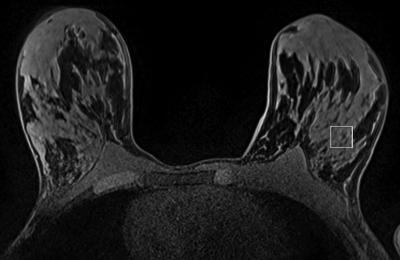

OAK BROOK, Ill. - A magnetic resonance spectroscopy (MRS) technique that monitors biochemical changes in tissue could improve the management of women at risk of breast cancer, according to a new study published online in the journal Radiology .

For the new study, researchers assessed 2-D localized correlated spectroscopy (L-COSY) as a noninvasive means to identify biochemical changes associated with a very early stage of cancer development known as the pre-invasive state.

The researchers performed L-COSY on nine women carrying the BRCA1 and 14 women with BRCA2 gene mutations and compared the results with those from 10 healthy controls who had no family history of breast cancer. All the patients underwent contrast enhanced 3-T MRI and ultrasound.

While no abnormality was recorded by MRI or ultrasound, L-COSY MRS identified statistically significant biochemical changes in women with BRCA1 and BRCA2 gene mutations compared to controls. The researchers found multiple distinct cellular changes measurable through L-COSY indicative of premalignant changes in women carrying BRCA gene mutations.